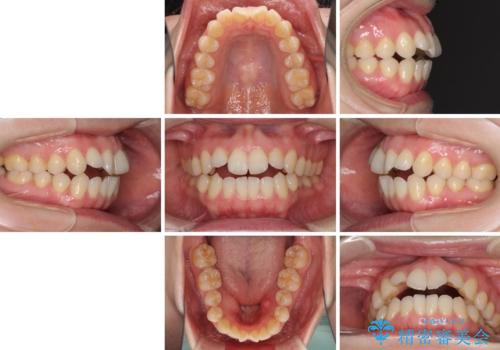

- 前歯の開咬を気にして来院された患者様です。

開咬の治療は、前歯を閉じるように動かすとともに、上下臼歯を圧下(骨内にめり込ませる)させることで進めて行きます。

インビザラインは臼歯の圧下を効果的に行えるため、インビザラインを用いて矯正治療を行うこととしました。